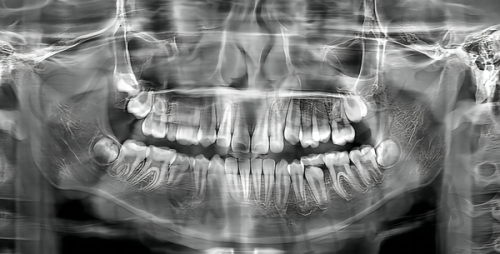

福州美可普口腔医院是一家连锁品牌,在数字化种植牙和隐形正畸技术方面成熟,性价比高。

特色亮点:数字化种植牙技术能让种植过程更精细、更安心,隐形正畸则让矫正牙齿变得更加美观和舒适。而且性价比高,能为患者节省不少费用。